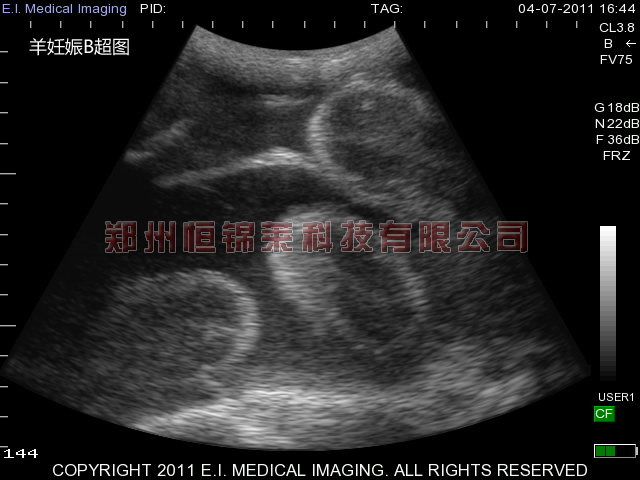

羊瘤胃积食使用羊用B超机观察

羊瘤胃积食就是通常所说的急性瘤胃扩张,在圈养羊群中比较常见,使用羊用B超机观察羊瘤胃,可以看到瘤胃充满而坚实,病羊精神委顿,食欲不振,严重时食欲废绝,四肢紧靠腹部、背弓起、眼无神。间有腹痛症状,如用后蹄踢腹部,头向左后弯,卧下又起立,等等。瘤胃的收缩力降低,频率减少,触诊时或软或硬,有时如面团,用指一压,即呈凹陷。羊用B超机检测B超图像显示大多数羊的反刍停止,走路不稳等。

发生瘤胃积食主要是因为喂养大量枯老硬草、干枯秸秆等草料,长期圈养使羊得不到应有的运动,饮水不足或者食用过多谷类饲料导致瘤胃酸中毒造成的。用羊用B超机可以看到羊瘤胃内容物充满且黏硬等症状可以判断为瘤胃积食。